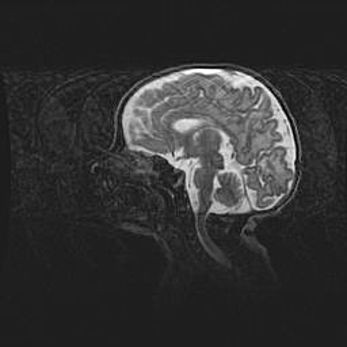

Неполная лизэнцефалия (пахигирия). Открытая гидроцефалия.

Возраст: 17 дней

Вес: 3110 г

Пол: мужской

Окружность головы: 33,5 см

Срок гестации: 35-36 недель

Лизэнцефалия—недоразвитие корковой пластинки и мозговых извилин в результате нарушения миграции нейронов коры. Поверхность мозговых полушарий гладкая. Микроскопически выявляется отсутствие нормальных слоев коры и скопление групп нейронов в подкорковом белом веществе.

Пахигирия—уменьшение числа вторичных извилин. В пораженном полушарии нервные клетки образуют толстый недифференцированный слой с неправильно расположенными нервными волокнами и группами гетеротопных клеток. Нервные клетки незрелые. Белое вещество истончено. При этом нередко аномально развит корково-спинномозговой путь.